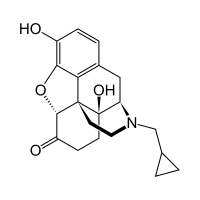

The pharmacodynamic response to an opioid depends upon the receptor to which it binds, its affinity for that receptor, and whether the opioid is an agonist or an antagonist. For example, the supraspinal analgesic properties of the opioid agonist morphine are mediated by activation of the μ1 receptor; respiratory depression and physical dependence by the μ2 receptor; and sedation and spinal analgesia by the κ receptor. Each group of opioid receptors elicits a distinct set of neurological responses, with the receptor subtypes (such as μ1 and μ2 for example) providing even more [measurably] specific responses. Unique to each opioid is its distinct binding affinity to the various classes of opioid receptors (e.g. the μ, κ, and δ opioid receptors are activated at different magnitudes according to the specific receptor binding affinities of the opioid). For example, the opiate alkaloid morphine exhibits high-affinity binding to the μ-opioid receptor, while ketazocine exhibits high affinity to ĸ receptors. It is this combinatorial mechanism that allows for such a wide class of opioids and molecular designs to exist, each with its own unique effect profile. Their individual molecular structure is also responsible for their different duration of action, whereby metabolic breakdown (such as N-dealkylation) is responsible for opioid metabolism.

Several semi-synthetic opioids were developed in Germany in the 1910s. The first, oxymorphone, was synthesized from thebaine, an opioid alkaloid in opium poppies, in 1914.[228] Next, Martin Freund and Edmund Speyer developed oxycodone, also from thebaine, at the University of Frankfurt in 1916.[229] In 1920, hydrocodone was prepared by Carl Mannich and Helene Löwenheim, deriving it from codeine. In 1924, hydromorphone was synthesized by adding hydrogen to morphine. Etorphine was synthesized in 1960, from the oripavine in opium poppy straw. Buprenorphine was discovered in 1972.[228]